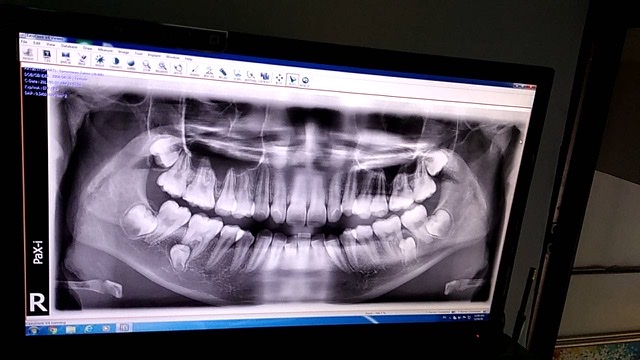

เราไปX-ray ฟันคุดมาค่ะ แบบนี้ผ่ายากไหมคะ เดี๋ยวจะมีผ่าเร็วๆนี้

หมอบอกว่าของเราหายากแต่คือเราไม่รู้ว่าจะผ่ายากไหม เรามีฟันคุด6ซี่ ต้องผ่าออกก่อนด่วน2ซี่